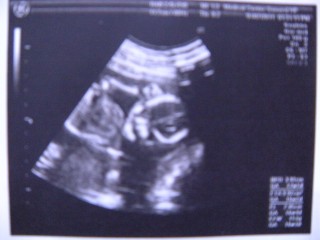

4Dで撮って貰った、やや斜め後ろ姿です。 あばらや背骨がくっきり映ってるのが見えます。 この時、残念ながら性別が分からなかったー! しっかり足を閉じられちゃってました(笑)